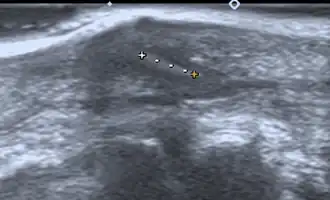

- Medical ultrasonography – used to locate glass, metal, pencil graphite, some plastics, stone, and some types of wood.[6]

Small wooden splinters (1–4 mm) distant from bones are most easily detected by ultrasonography, while CT scan and magnetic resonance imaging have higher sensitivity for those near bones.[7]